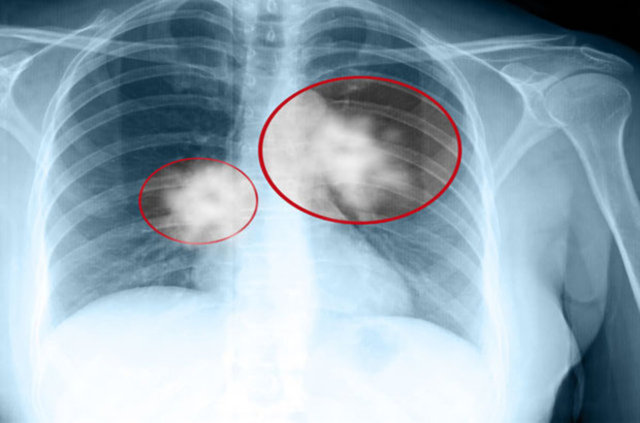

Akciğer kanserinin sinsi bir şekilde ilerleyerek ileri evrelerde ortaya çıktığını söyleyen Doç. Dr. Keskin, hastalığın erken evrede tanı almasının önemli olduğunu vurguladı.

Doç. Dr. Keskin, "Yapılan araştırmalar başta sigara kullananlar olmak üzere akciğer kanseri riski altında olanların 50 yaş ve üzerinde mutlaka tarama yaptırmasının gerekliliğine işaret ediyor. Bu taramalar sonucu erken evrede tanısı konulabilen akciğer kanseri, uygulanan tedavilerle tamamen ortadan kaldırılabilir" diye konuştu.